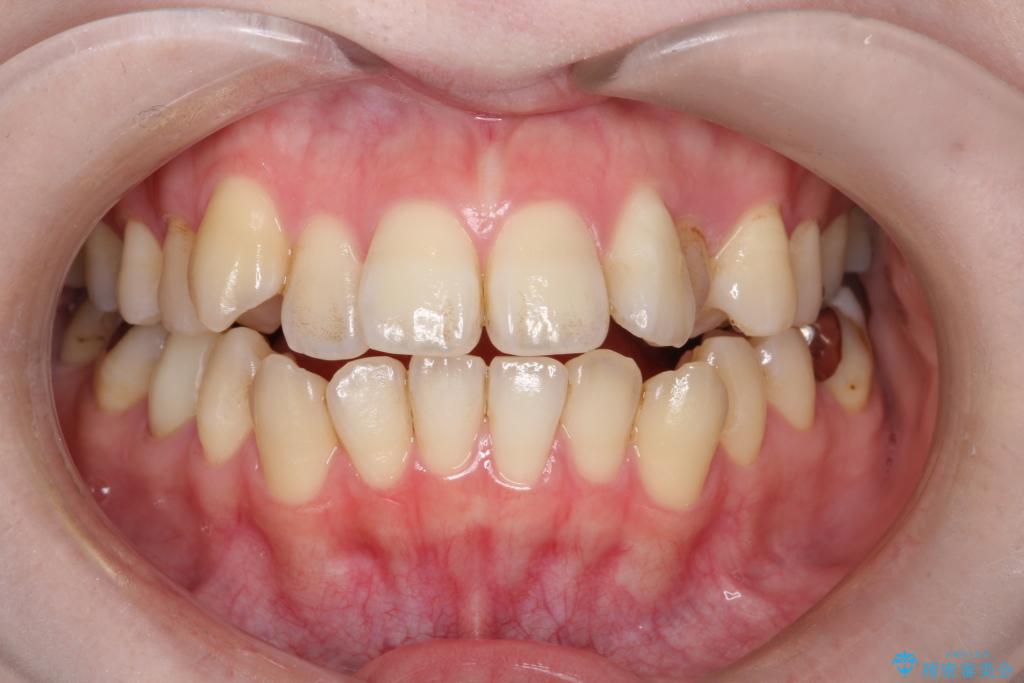

開咬や歯列のデコボコが改善され、見た目だけでなく咬み合わせの機能面も大きく向上し、大変ご満足いただけました。

また、治療期間も比較的短期間で終了することができました。